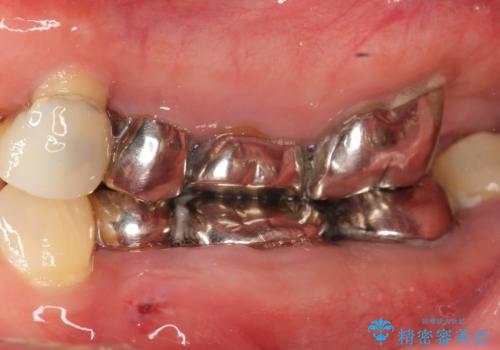

全顎的に多発した虫歯治療

自家歯牙移植